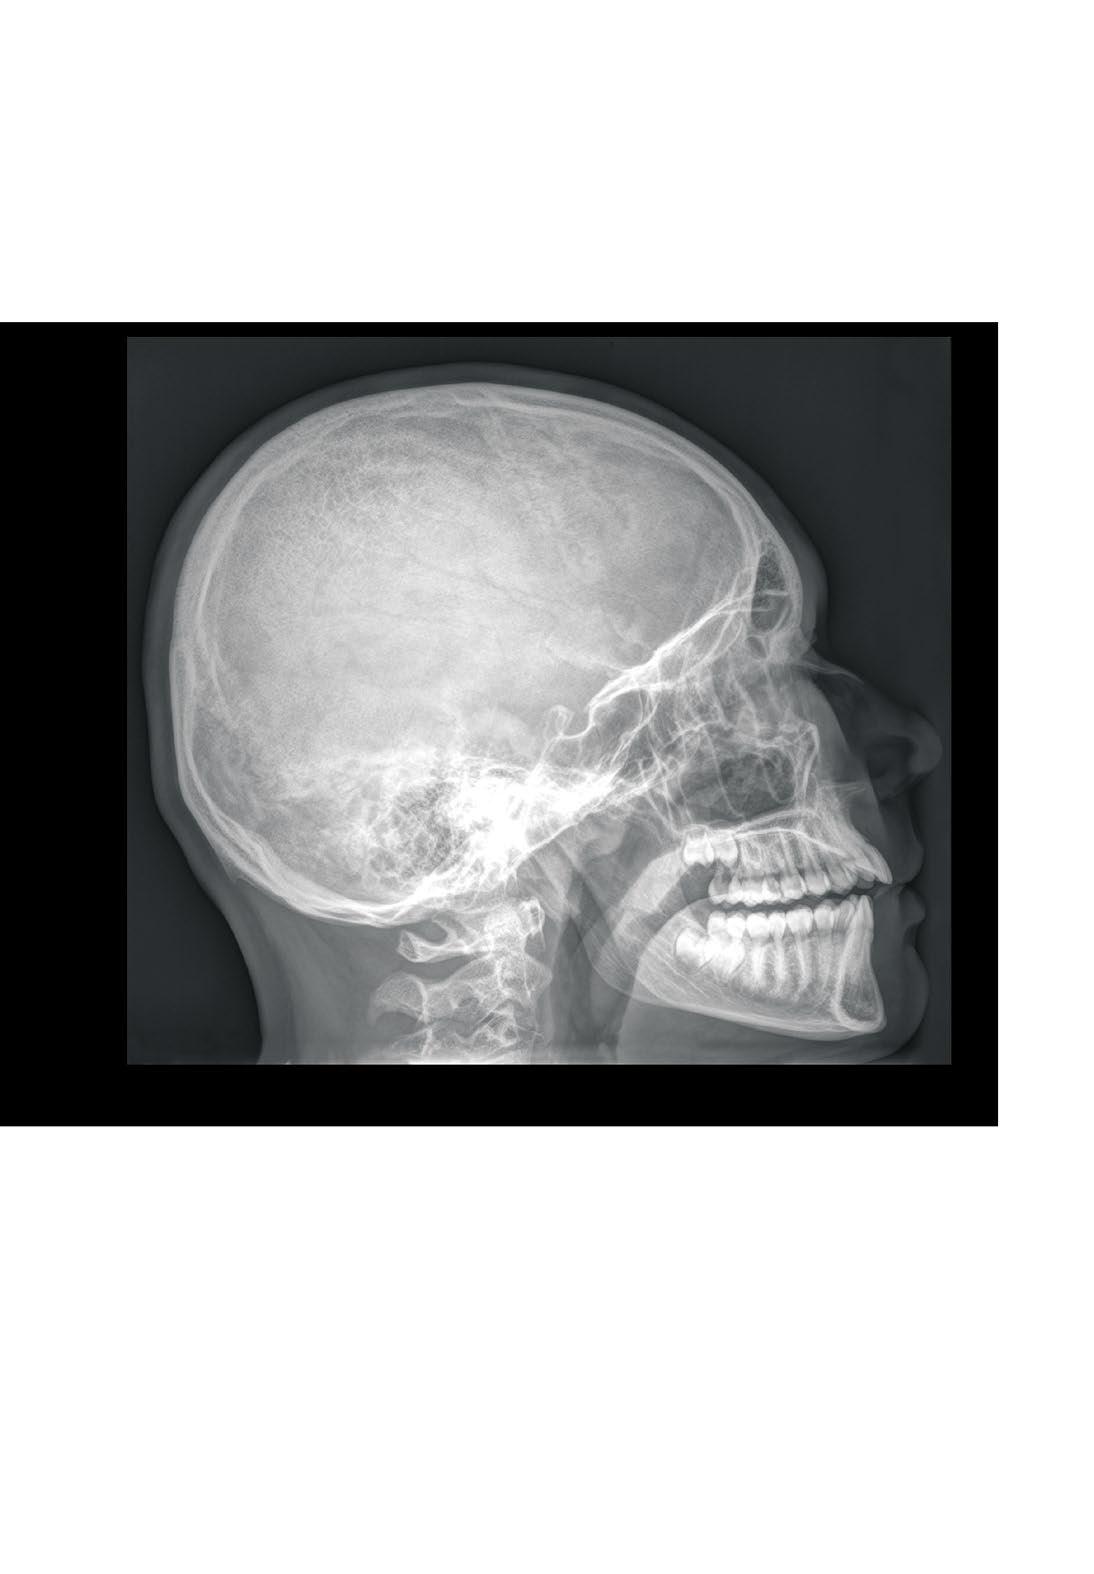

Skull, X-ray, lateral view, boy, 15 years Hlava

sutura coronalis sinus sphenoidalis

Cranium, RTG lebky, boční projekce, chlapec, 15 let

processus condylaris arcus atlantis anterior

dens axis canalis mandibulae processus mastoideus

cellulae mastoideae fossa hypophysialis

processus palatinus maxillae

lamina horizontalis ossis palatini

foramen palatinum majus

choanae

foramen ovale

foramen spinosum

tuberculum pharyngeum

canalis caroticus

processus styloideus

fossa jugularis

condylus occipitalis

foramen magnum

crista occipitalis externa